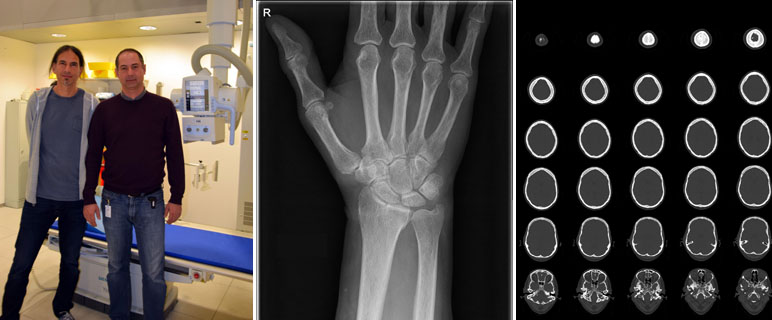

Die EuroSafe Imaging Initiative der Europäischen Gesellschaft für Radiologie (ESR, European Society of Radiology) wurde 2014 gestartet, um den Strahlenschutz im medizinischen Bereich zu forcieren und zu verbessern. Neben der Optimierung der Untersuchungen und der Bildqualität zielt die Initiative auch auf die Verbesserung der Kommunikation zwischen PatientInnen und medizinischen Personal ab. Im Rahmen der Überprüfung der EuroSafeImaging-Qualitätskriterien hat das Department Radiologie der Medizinischen Universität Innsbruck die höchst mögliche Punktzahl (fünf Sterne) erhalten. Die beiden zum Department gehörenden Kliniken werden von Univ.-Prof.in Dr.in Elke Gizewski (Neuroradiologie) und o.Univ.-Prof. Dr. Werner Jaschke (Radiologie) geleitet.

Die hervorragende Bewertung ist eine Auszeichnung für die seit Jahren gesetzten Maßnahmen zur Qualitätssicherung und -kontrolle. Ein wichtiges Ziel ist der sichere Umgang mit der verwendeten Strahlung und nach Möglichkeit eine Weiterentwicklung der verwendeten Technik zur Reduzierung der verwendeten Dosis. PatientInnen erhalten die höchstmögliche Sicherheit. „Der erste Schritt zur Dosisreduzierung ist die genaue Dokumentation der verwendeten Strahlenintensität. Nur wenn wir die Dosis genau kennen, können wir auch Maßnahmen zur Optimierung setzen“, erklären Dr. Michael Verius und Mag. Pavle Torbica. Die beiden Medizinphysiker sind die Strahlenschutzbeauftragten am Department Radiologie. Gemeinsam mit ihrem Kollegen Mag. Robert Eder haben sie eine Software entwickelt, die bereits seit Mitte 2012 angewendet und laufend verbessert wird. „Damit können wir für jede Patientin und jeden Patienten die verwendete Strahlendosis erfassen, speichern und analysieren“, erklärt Michael Verius. Damit nimmt das Department Radiologie eine Vorreiterrolle in Bezug auf das Dosis-Management in Österreich ein. „Für die behandelnden ÄrztInnen ermöglicht die Datenerfassung es frühzeitig zu erkennen, wenn vorgeschriebene Belastungshöchstgrenzen überschritten werden“, sagt Pavle Torbica. Die erfassten Daten sind auch relevant für die Weiterentwicklung auf dem Gebiet der Radiologie. Im Rahmen von Forschungsprojekten werden die Werte analysiert. Die Erkenntnisse sollen dabei helfen, die Strahlendosis bei einer Untersuchung oder Behandlung weiter zu optimieren, ohne die Bildqualität zu verschlechtern. Insbesondere im Bereich der Computertomographie (CT) sind hier noch weitere Verbesserungen möglich. „CT-Untersuchungen machen zwar nur 9 bis 10 Prozent aller Untersuchungen aus. Ihr Anteil an der Kollektivdosis beträgt aber trotzdem 65 bis 70 Prozent“, weiß Michael Verius. Ähnliches gilt für durchleuchtungsgesteuerte therapeutische Eingriffe wie z. B. die katheterbasierte Behandlung von Gefäßerkrankungen.